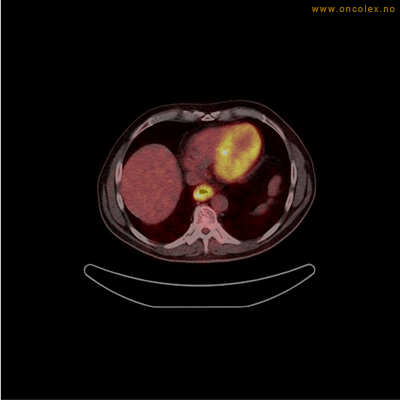

Vev som tar opp mer radioaktivt stoff, synes som hvite områder som lyser opp mer i forhold til annet vev som tar opp mindre sukker.

Adenokarsinom distalt i spiserør. Fysiologisk opptak i hjertemuskulatur.

Adenokarsinom langt nede i spiserøret.